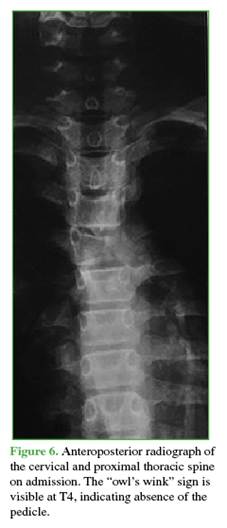

On admission, anteroposterior radiography revealed absence of the pedicle image in the affected vertebra, a radiographic sign known as the “owl’s wink” (Figure 6).12

The lesion involved zones 3-6 and levels III and IV of the Weinstein-Boriani-Biagini classification.11 Complementary imaging studies showed multiple septated cysts with fluid-fluid levels. A simple bone cyst with expansile and compressive features was ruled out, as was vertebral hemangioma (Figures 7 and 8). This case was also interpreted as an Enneking grade 3 ABC.13